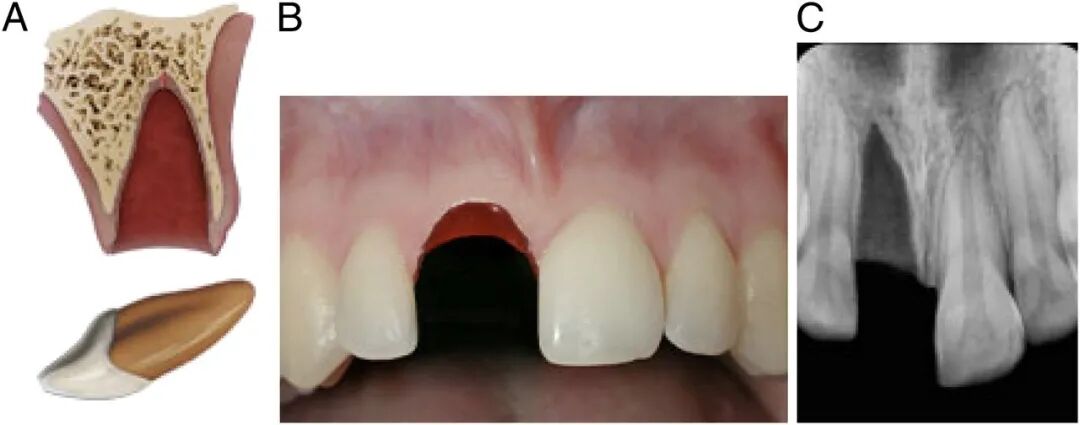

2、牙齿摔断

牙齿摔断依旧需要家长先找到掉的那半截牙,不过不用考虑保持细胞活性,所以不用泡牛奶了,找不到掉牙也没关系,尽快送医。

断牙治疗主要看断开的位置有没有暴露牙神经,分牙冠折断、牙根折断和冠根均折断等三种类型。

没有暴露牙神经,处理就比较简单。只需将牙釉质断面较锐利的地方磨光滑,不扎舌头即可。

也可以采用断冠再接的办法,把磕掉的那半截牙冠再粘回去。

如果牙齿摔断之后,牙冠碎了或者找不到了,就在保护牙髓之后,用材料对牙齿进行修复。

如果牙齿断得比较靠近牙根,或者摔裂了,裂缝延伸到牙根,这些情况可能会伤到牙神经,处理起来复杂一些。

图源:AAP

为了防止牙神经感染,牙医通常采用一些材料,覆盖到这个露出神经的表面,然后再用材料把牙齿外形严密封闭。

如果牙齿磕断时间较长,露出的牙神经比较多,就采取牙髓切断术把受感染的这一部分牙神经去掉,把健康的牙髓保留下来,让牙根继续生长和发育。